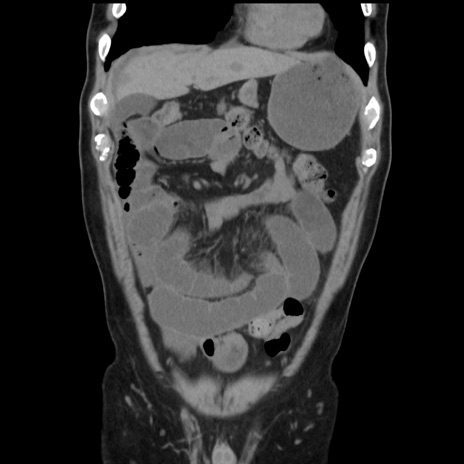

症例16(冠状断像)

【症例】 70歳代男性

【主訴】 腹痛、嘔吐

【現病歴】 約1ヶ月前より間欠的に腹痛と嘔吐あり、当院消化器内科を受診したところCTで多発する肝臓のLDAを指摘され、精査中であった。以降は消化器症状は安定していたが、2日前より嘔気と腹痛があり、同日より排便・排ガスが消失した。改善認めず、 本日、救急外来を受診した。

【既往歴】 大腸ポリープ切除後。

【身体所見】意識清明・会話良好、BT 36.3℃、BP 127/80mmHg、 P 80bpm、腹部:膨満あり、平坦・軟、上腹部正中および下腹部正中に圧痛あり、反跳痛なし、筋性防御なし。

【データ】WBC 7200、CRP 0.77